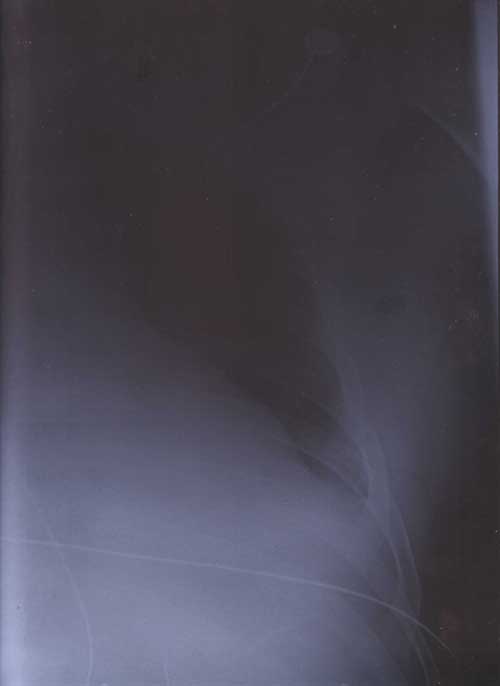

X Rays

22nd January 2000